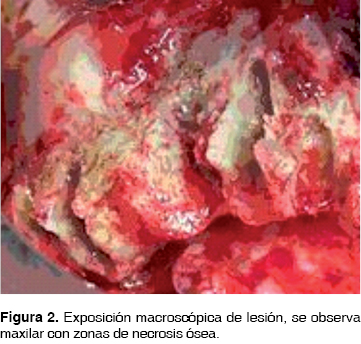

Clínicamente presenta una fístula en región de premolar superior izquierdo de 2 x 1 mm, halitosis severa, astenia, adinamia, cefalea holocraneana izquierda, enfermedad periodontal crónica, ausencia de múltiples órganos dentarios. La tomografía computarizada demuestra áreas líticas con bordes escleróticos con reacción perióstica y secuestro óseo (Figura 1). En biometría hemática presenta valores de hemoglobina de 14 g/dL, leucocitos de 7.44 cpm, glucosa de 109 g/dL. Se inicia tratamiento farmacológico con clindamicina 600 mg IV cada 8 hrs. y ceftriaxona 1 g IV cada 12 hrs. Se decide realizar hemimaxilectomía subtotal bajo anestesia general inhalatoria balanceada, mediante abordaje circunvestibular de 6 cm con disección de tejidos hasta exposición de la lesión, observando zonas de necrosis ósea, (Figura 2) obteniendo espécimen quirúrgico de 3 x 3 cm con áreas de necrosis de color negro y fétido. Se verifican macroscópicamente bordes óseos libres de lesión y se suturan los tejidos con sutura ácido poliglicólico 3 ceros.